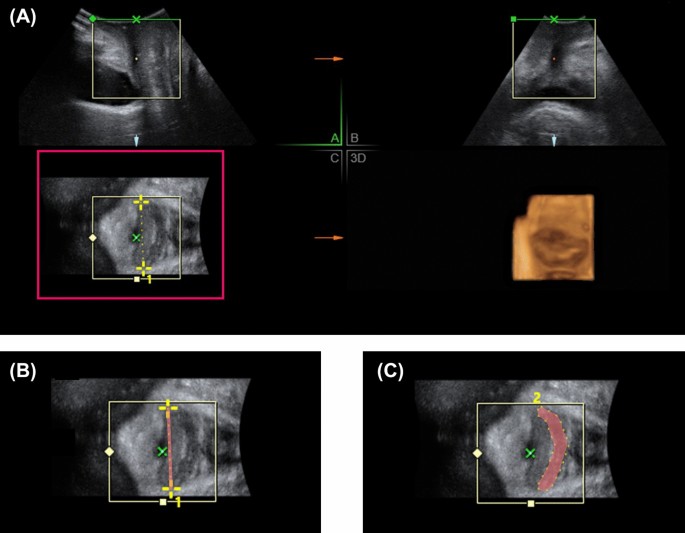

Before and 6 months after treatment, a 3-D transperineal ultrasound was applied for vaginal topography to those women with SUI received Er:YAG vaginal laser treatment. The ultrasound was performed by two experienced urogynecologist (CY Long and KL Lin) according to KMUH-TPUS protocol. In the protocol, the 3-D ultrasound was performed under a supine posture with bilateral hips and knees flexion and slightly spreading legs. A convex probe was placed over perineum. The measurement was done on the midsagittal plane. Mode of rendered volume was obtained on relax without pelvic muscle contraction to obtained an axial plane of pelvis over the panel C in Fig. 1A. The vagina was recognized as hypoechoic area between urethra and anal canal in genital hiatus. Vaginal width (the red line in Fig. 1B) and cross-sectional area of vagina (the red-marked area in Fig. 1C) were measured at level of proximal, middle and distal part of vagina. The middle vagina was defined as the vagina at bladder neck level. The proximal vagina was defined as 2 cm inside from the bladder neck, and the distal vagina was 2 cm outside from bladder neck. The sequential images of vaginal width and area of a same patient before and after treatment at different levels of vagina were shown in Fig. 2.

The measurement of vaginal topography via transperineal ultrasound. A convex probe was placed over perineum. The measurement was done on the midsagittal plane. Mode of rendered volume was obtained on relax without pelvic muscle contraction to obtained an axial plane of pelvis over the panel (C) in (A). The vagina was recognized as hypoechoic area between urethra and anal canal in genital hiatus. Vaginal width (the red line in B) and cross-sectional area of vagina (the red-marked area in C) were measured at level of proximal, middle and distal part of vagina.